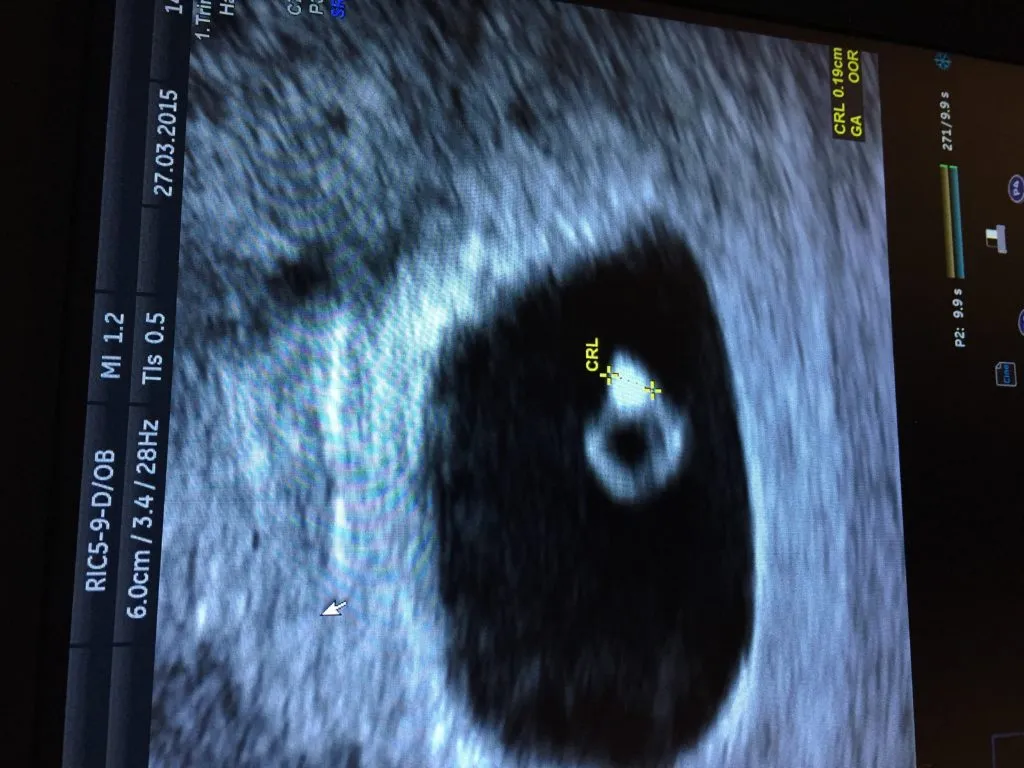

Około 4-5 tygodnia ciąży (licząc od pierwszego dnia ostatniej miesiączki) w USG dopochwowym zazwyczaj widoczny jest już pęcherzyk ciążowy. To mała, czarna, okrągła struktura w jamie macicy, która świadczy o tym, że ciąża rozwija się w prawidłowym miejscu. Jej obecność jest pierwszym, pewnym sygnałem ciąży widocznym w obrazowaniu.

Między 6. a 7. tygodniem ciąży w USG dopochwowym pojawia się zarodek, a co najważniejsze, widoczna staje się jego akcja serca. To ostateczne potwierdzenie żywej ciąży, które rozwiewa wszelkie wątpliwości. Warto również wspomnieć, że około 5-6 tygodnia ciąży, wewnątrz pęcherzyka ciążowego, często widoczny jest pęcherzyk żółtkowy, który odżywia zarodek na bardzo wczesnym etapie rozwoju.